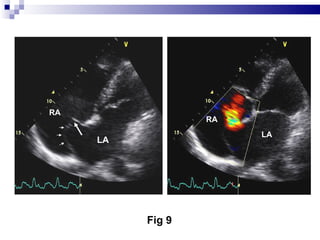

LA LA RA RA Fig 9

LA LA RARA Fig 9